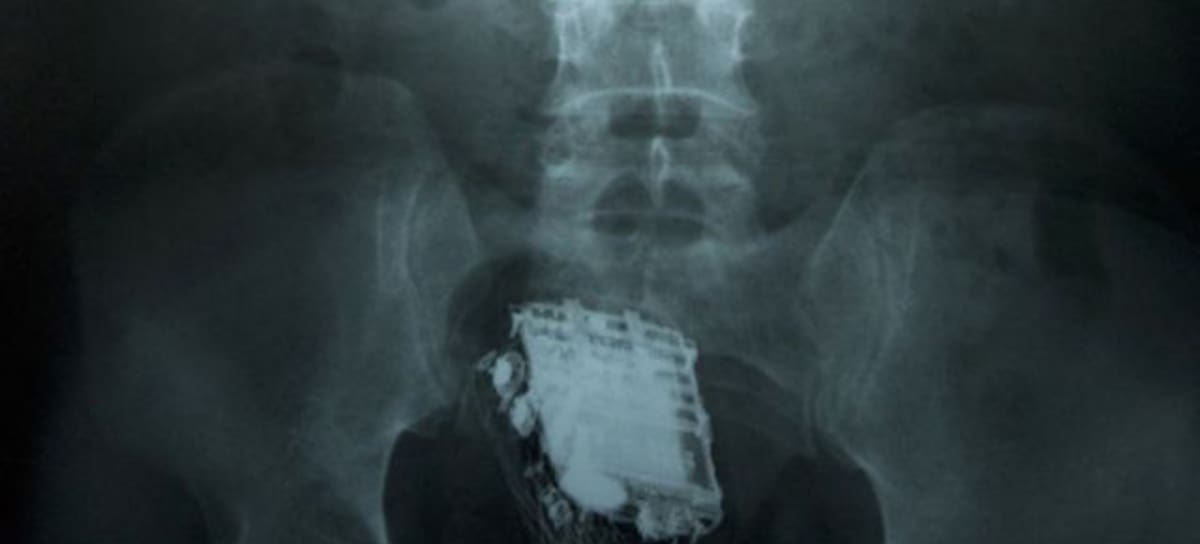

El preso fue enviado al Hospital donde una radiografía revelo que, además de llevar un móvil metido en el trasero, también llevaba un “kit de manos libres”.